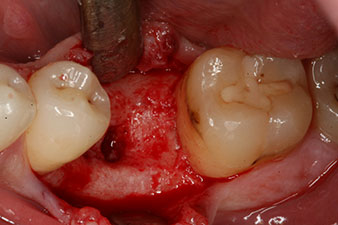

Fig. 1: Initial clinical situation after healing of extraction alveolus 36: The bone base is wide and there is sufficient keratinized gingiva.

A 28-year-old patient with a history of heavy smoking had to have tooth 36 extracted as a result of recurring apical periodontitis.

Due to the generally intact neighbouring teeth the only way to fill the gap was an implant.

However, six weeks after the extraction incomplete ossification was found after preparation of the mucoperiosteal flap in the region of the former mesial alveolus.